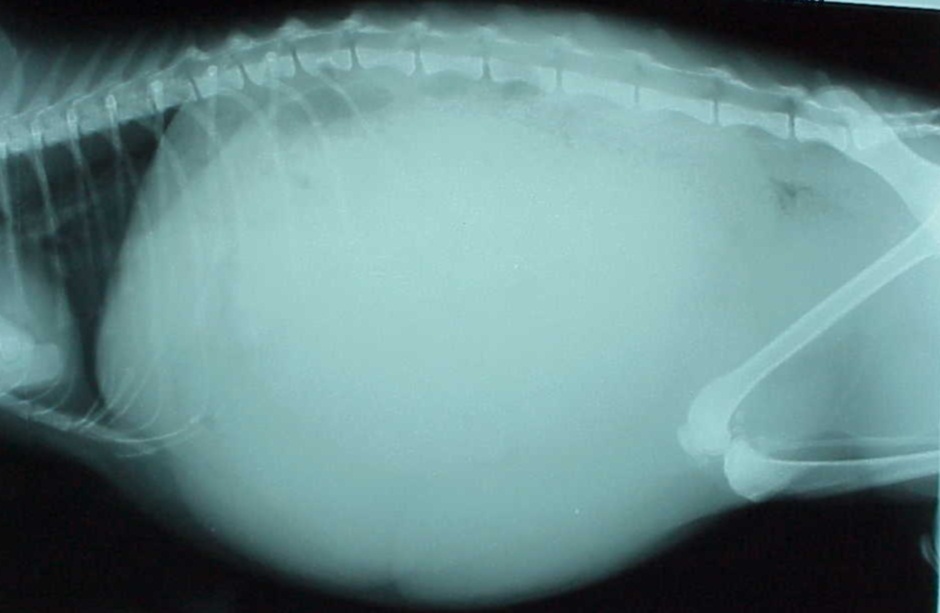

XRay image of obese cat with complete intestinal obstruction Cat Stomach Tumor X Ray A cat with stomach cancer rarely shows symptoms and therefore, its diagnosis and treatment are difficult. The aggressive, painful cancer leiomyosarcoma affects muscles in a cat’s stomach and intestines. Our veterinary oncology team in matthews describes signs of. What is stomach cancer in cats? Leiomyosarcoma is a cancer occurring in the stomach of cats and the intestines. Some of the. Cat Stomach Tumor X Ray.

Xray Image Abdominal Distent Cat Show Foto de stock 1412305625 Cat Stomach Tumor X Ray Our veterinary oncology team in matthews describes signs of. Some of the signs of this cancer are also symptoms of common stomach disorders,. Leiomyosarcoma is a cancer occurring in the stomach of cats and the intestines. What is stomach cancer in cats? A cat with stomach cancer rarely shows symptoms and therefore, its diagnosis and treatment are difficult. The aggressive,. Cat Stomach Tumor X Ray.